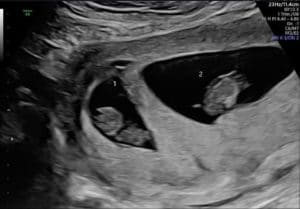

Oregon Essure Reversal Mom, 9 Weeks With Twins!

Twins After Reversing Essure

oregon-essure-reversal-mom-has-twins-after-reversing-essure-with-dr-monteithDr. Monteith has made my dreams come true! I am now 9 weeks pregnant with twins.

Even with having 3 years between my surgery and getting pregnant, the wait has been worth it.

My twins are in the perfect spot and got to see their hearts beat together.

Thank you Dr. Monteith!

Patient age: 38

Tubal ligation type: Essure

Patient hometown: Creswell, Oregon